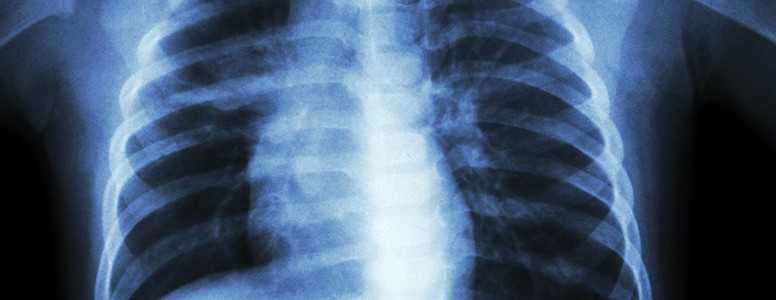

Having type 2 diabetes as an adult makes you seven times more likely to develop tuberculosis (TB), according to new research.

The researchers examined the medical data of 69 Australian patients, all of whom had TB at some point between 1995 and 2014. Within this group of TB patients, 23 per cent also developed type 2 diabetes.

The researchers then compared this data to that of the general population and found a strong association between diabetes and tuberculosis. Patients with diabetes were seven times more likely to have tuberculosis.